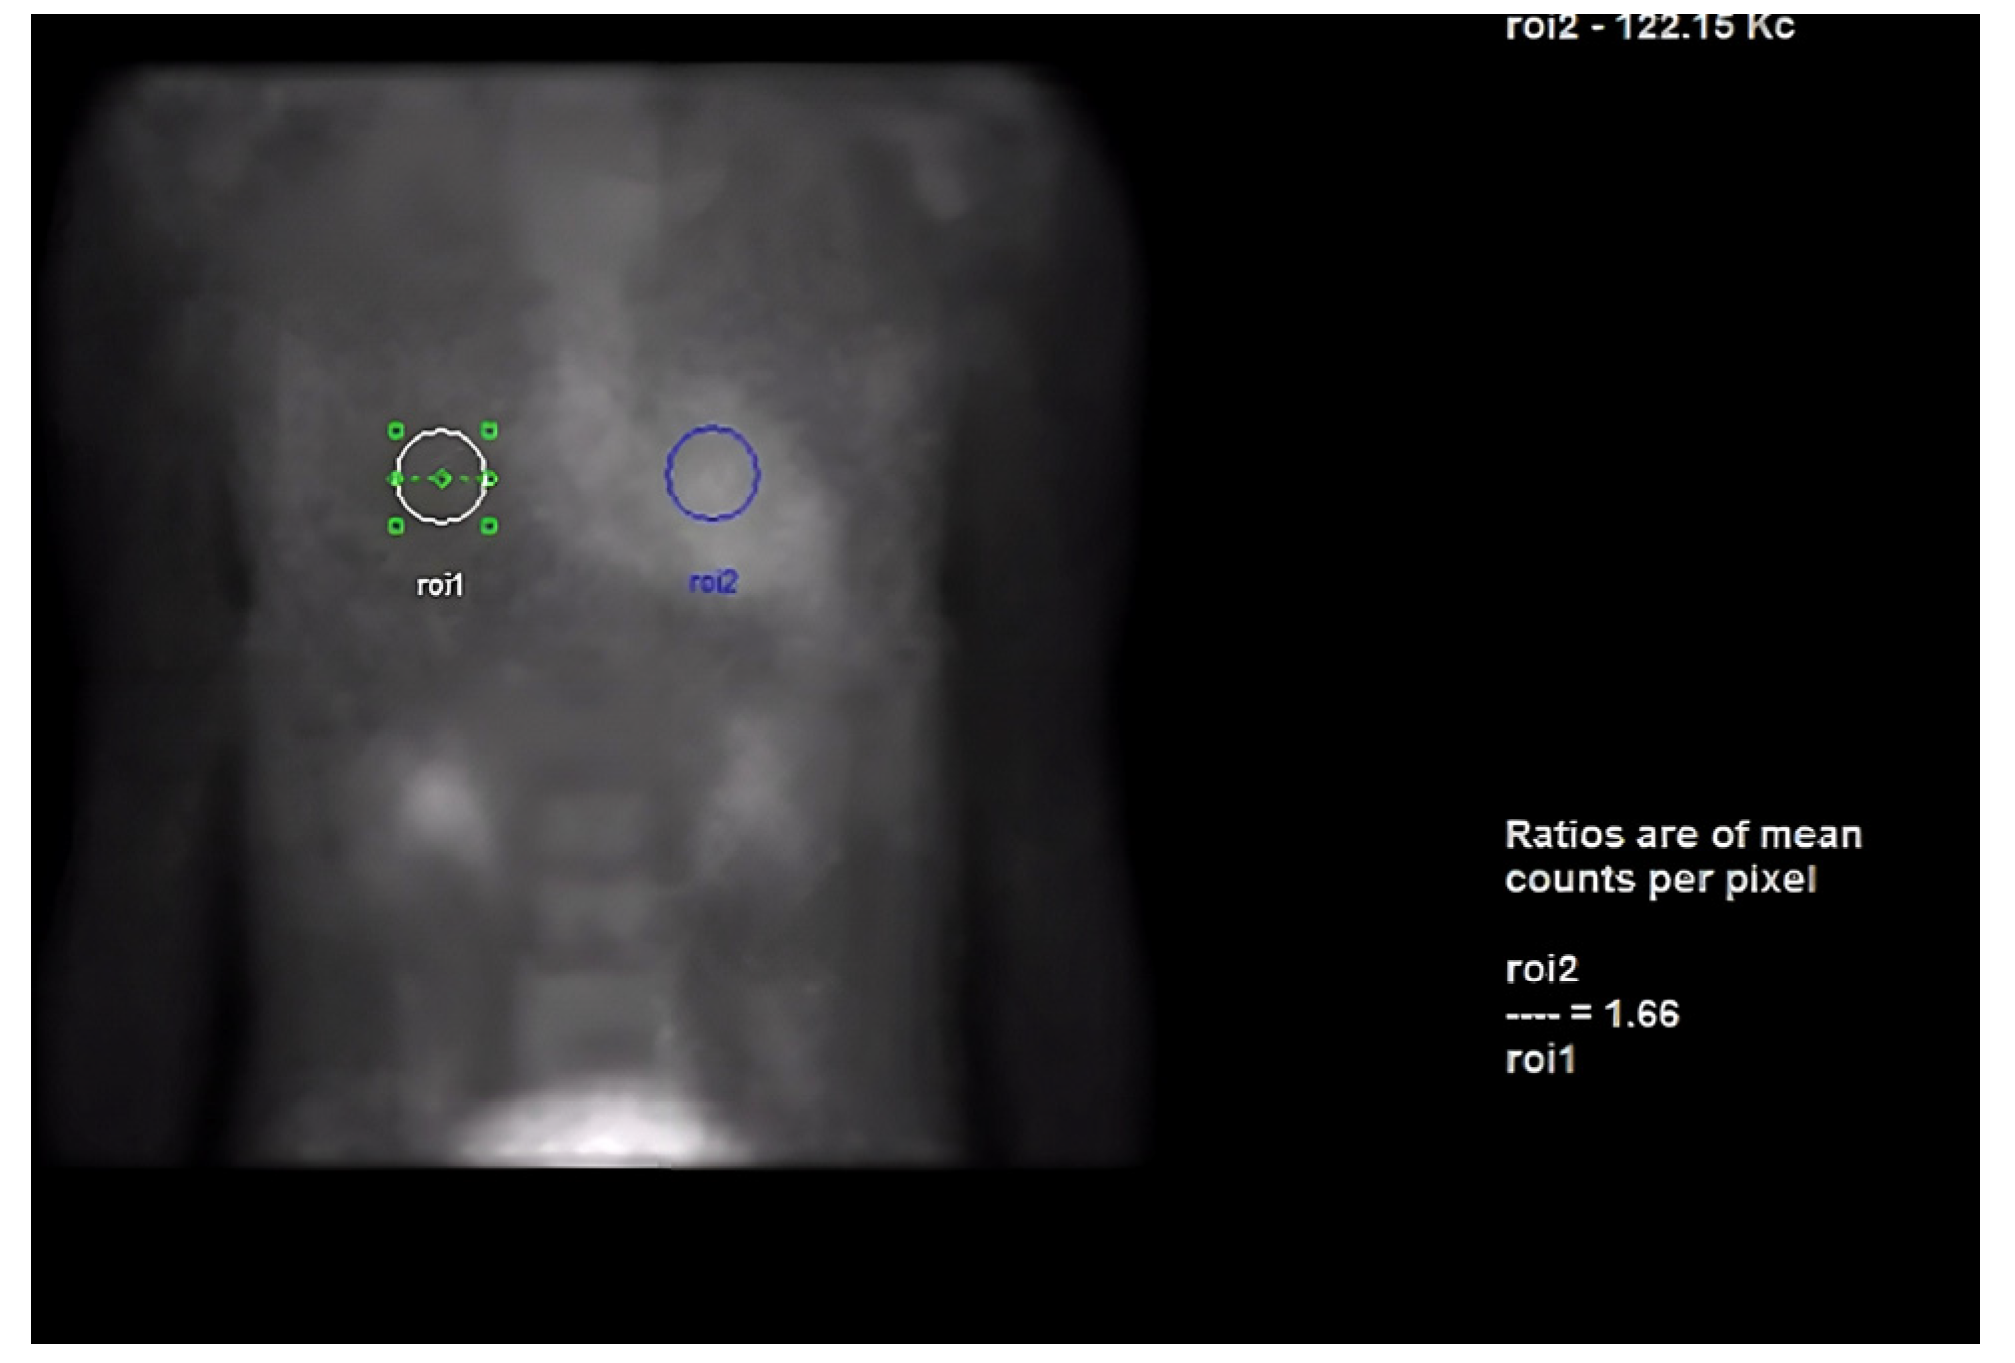

Next, we performed a 99Technetium pyrophosphate (99mTc-PYP) planar scintigraphy (Figure 4). A quantitative analysis of the heart retention pattern showed a heart-to-contralateral lung (H/Cl) ratio of 1.66 (Figure 5), strongly suggestive of amyloid deposition. To differentiate the type of cardiac amyloidosis, genetic testing was obtained and revealed a heterozygous pathogenic mutation in the TTR gene, diagnostic for TTR amyloidosis.

Radionuclide bone scintigraphy uses a bone-avid, phosphate-based isotope (99mTc-PYP) as a noninvasive way to diagnose ATTR. Phosphate-calcium binding seems to play an important role in the myocardial uptake of tracers, though the exact mechanism is unknown. Increased tracer accumulation in ATTR may suggest it has a higher calcium level than AL, and/or the duration of amyloid deposition increases uptake as ATTR has a more indolent course. Scoring cardiac uptake of the tracer is done via a semi-quantitative method using the Perugini grading scale (graded from 0–3). It visually compares tracer uptake in the myocardium and ribs of the planar image. 99mTc-PYP with abnormal uptake (grade 2 or 3) in the absence of a monoclonal gammopathy has a specificity and positive predictive value of 100% for diagnosing ATTR-CA. However, genotyping is still required to differentiate hATTR and wtATTR. If hATTR is present, first-degree relatives should be tested for the identified variant [25]. A heart-to-contralateral lung ratio > 1.5 has a 97% sensitivity and 100% specificity in differentiating ATTR from AL [28]. In patients with a monoclonal gammopathy, scintigraphy alone cannot be used to diagnose ATTR, and an endomyocardial biopsy (EMB) is required for diagnosis. Currently, imaging techniques allow for an accurate and noninvasive method to diagnose ATTR without the need for confirmatory myocardial biopsy. However, if you need to differentiate ATTR with concomitant MGUS from AL, an EMB is indicated. Lastly, a plasma cell dyscrasia with equivocal cardiac imaging findings is another indication for EMB [28].

Figure 5. Heart-to-contralateral ratio was calculated by drawing a region of interest over the heart, mirroring it to the contralateral chest, and calculating the ratio of heart ROI to contralateral chest ROI mean counts. The representative image demonstrates a H/CL ratio of 1.6. (H/CL, heart-to-contralateral; ROI, region of interest).